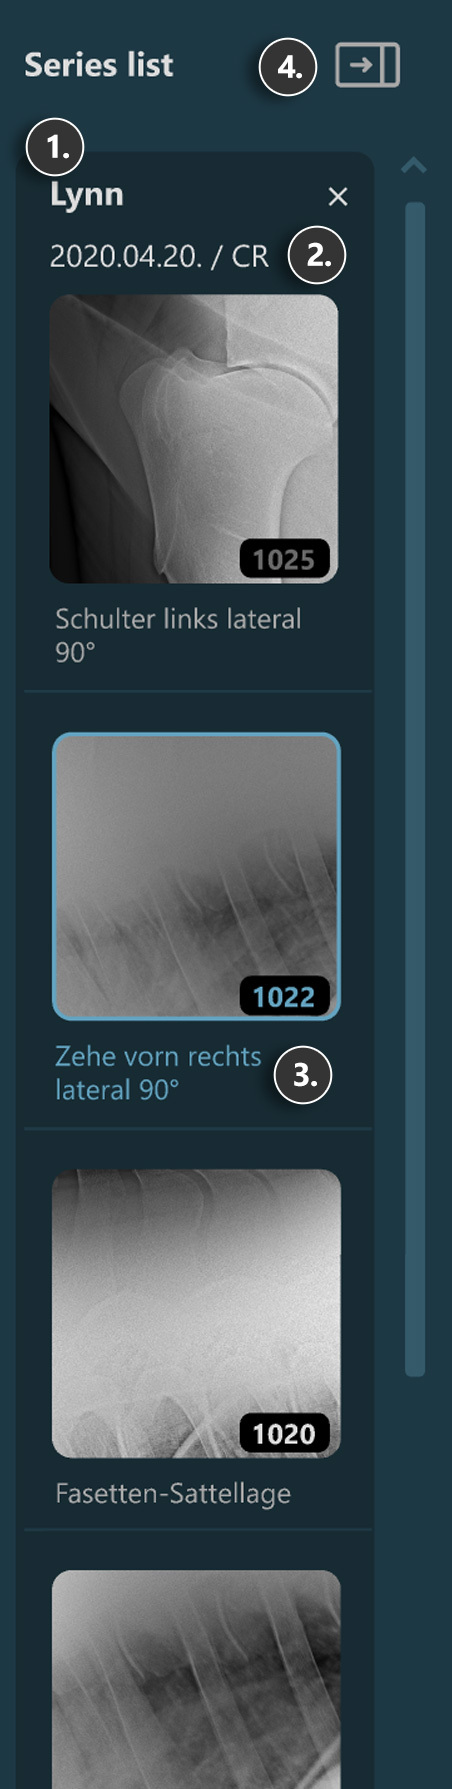

Sections of the VisioVIEW Viewer¶

The VisioVIEW Viewer consists of several sections, each tailored to a specific purpose. Below is a detailed description of each section.